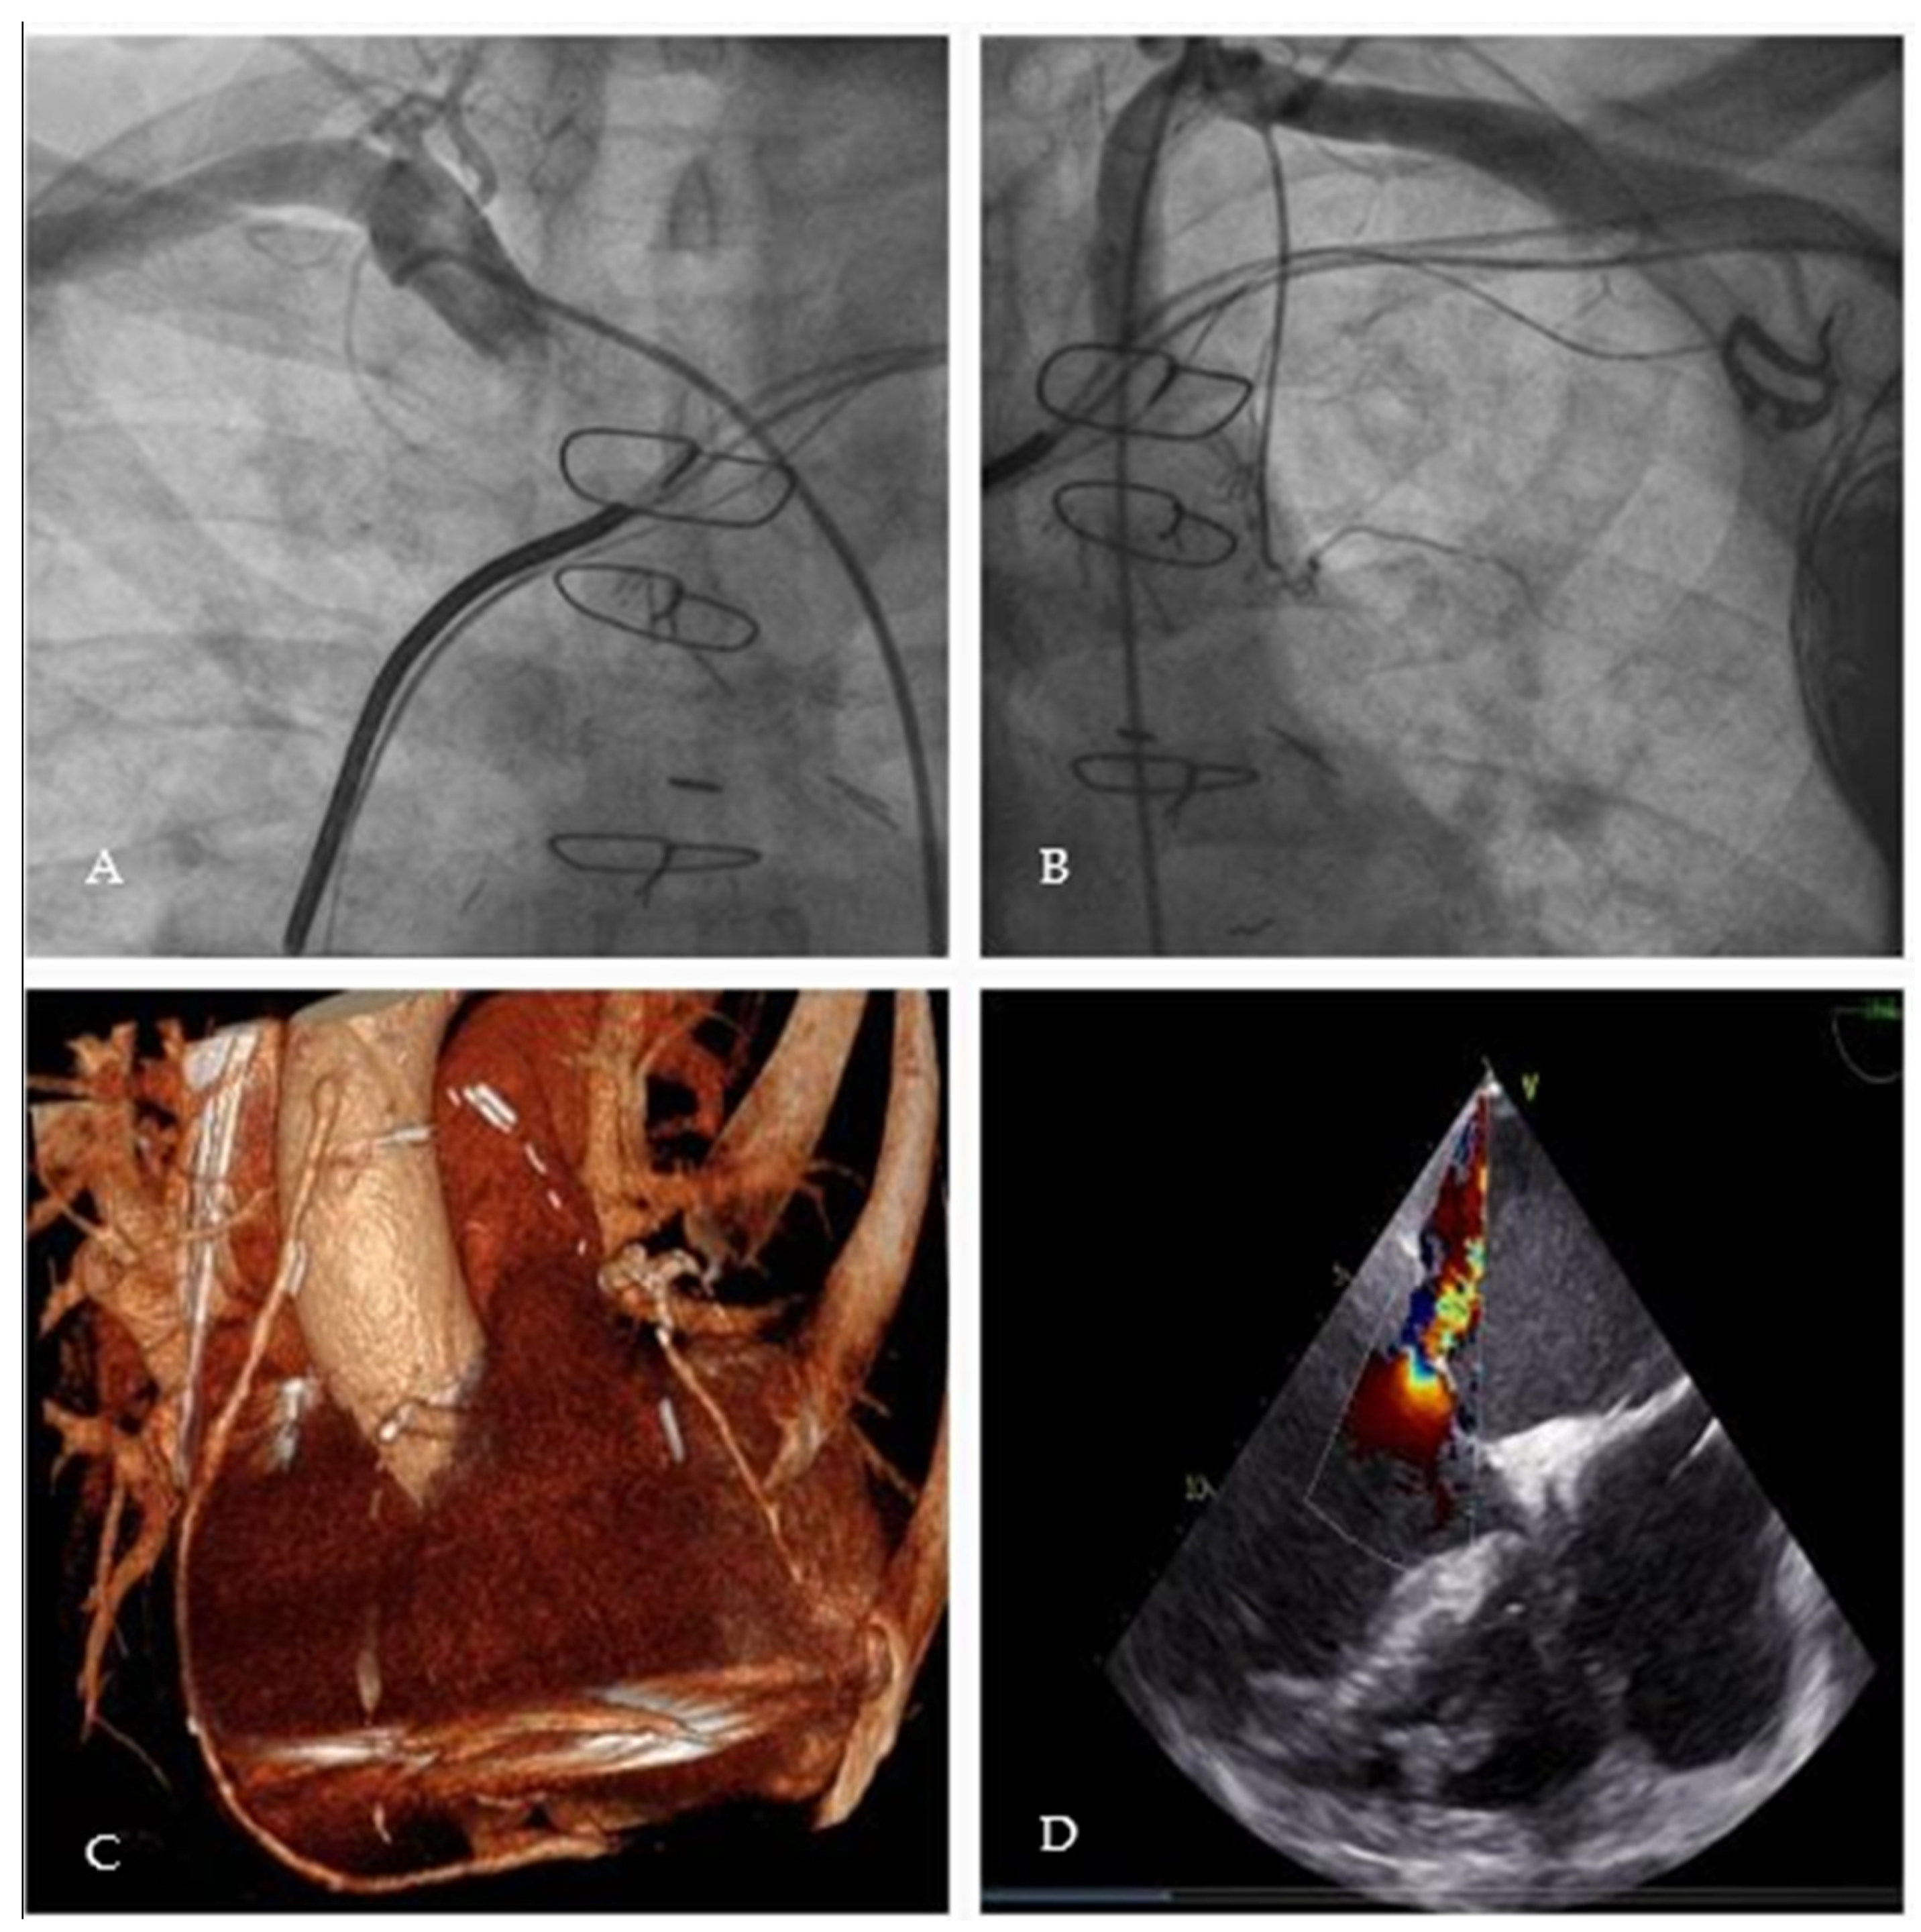

2. Case Presentation